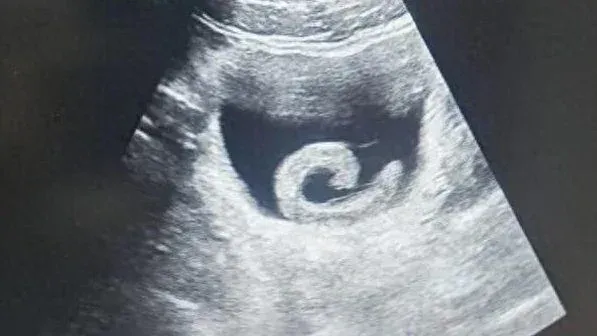

อาการปวดที่รุนแรงทำให้ "เจิ้ง" จำเป็นต้องเข้ารับการรักษาที่ห้องฉุกเฉิน ของโรงพยาบาลในพื้นที่ทันที ซึ่งแพทย์รู้สึกตกใจเมื่อได้ทราบสาเหตุ โดยภาพอัลตราซาวด์ยืนยันว่า "มีปลิงอยู่ในกระเพาะปัสสาวะจริง" แพทย์จึงเตรียมผ่าตัดฉุกเฉิน เพื่อเอาปรสิตออกและช่วยชีวิตของเขาทันที...